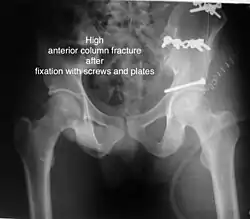

Anterior column This fracture is uncommon, typically occurring when the injuring force is applied from the side, against the greater trochanter of the femur bone, as in a fall on the side or being hit on the side. Depending on the location, the fractures are described as very low, low, intermediate and high anterior column fracture. Anterior column + posterior hemi transverse In this variety of fractures, the posterior or ilio ischial column is broken as a transverse fracture, while the anterior or ilio pubic column is broken into multiple pieces. Part of the weight-bearing dome in this variety of fractures is still attached to that part of the iliac wing, which forms part of the iliac joint. This type of injury has to be differentiated from both column fractures, where the weight-bearing dome is a floating piece not attached directly to the bone-forming sacroiliac joint.

Typically, it is caused by a combination of forces acting on the hip through the femoral head. All three X-ray views plus a CT scan are a must for the diagnosis and management of this complex injury. In this injury, non-operative treatment rarely gives satisfactory results. Surgical management is ideal. The choice of approach rests with the surgeon but going from the front or anterior approach is necessary. The posterior injury may be tacked with the anterior approach by an experienced surgeon. If the patient is unfit to undergo major surgery due to any reason, longitudinal traction to achieve secondary congruence of the hip may help to restore hip function, though partially.

The final management depends on the size of the fragment(s), stability and congruence of the joint. In some cases traction for six to eight weeks may be the only treatment required; however, surgical fixation using screw(s) and plate(s) may be required if the injury is more complex. The latter treatment will be called for if bone fragments do not fall into place, or if they are found in the joint, or if the joint itself is unstable.